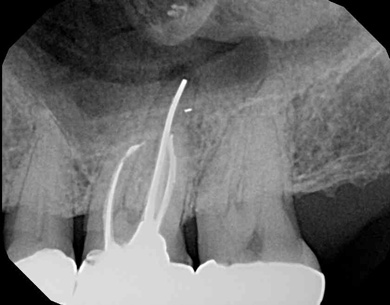

Fig 3. Tooth No. 14 was treated with silver points. In Figure 2, tooth No. 18 with mesial canals treated with Sargenti paste. The hallmark radiographic appearance of this technique is the light radiopacity within the canal system, as in Figure 3.

Figure 3